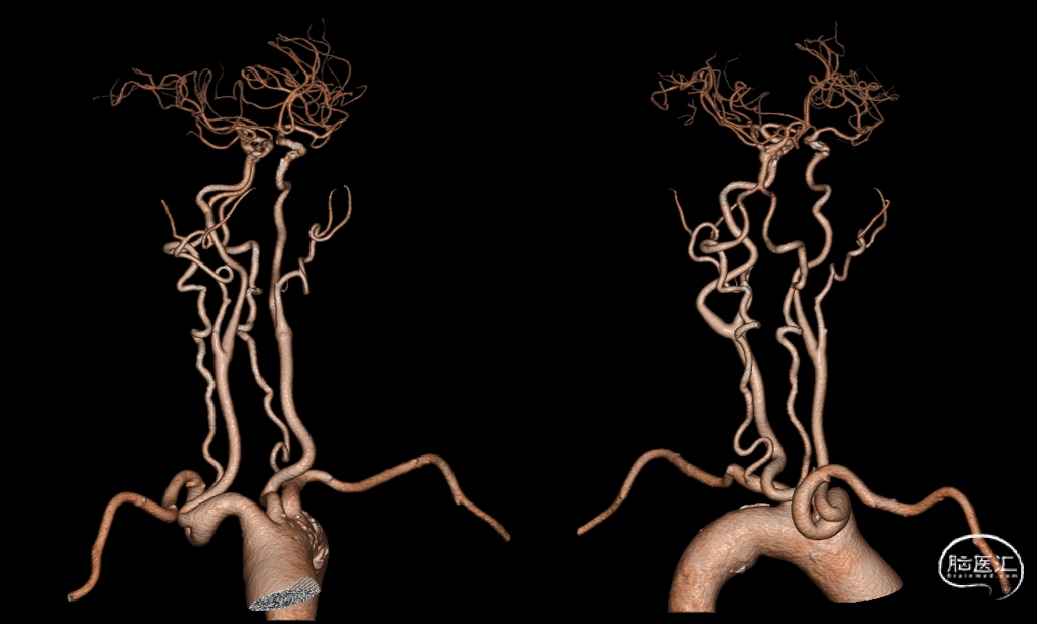

头颅CTA:基底动脉中段夹层动脉瘤。

颈部CTA。

3D造影:基底动脉夹层动脉瘤有多个瘤囊,最大瘤囊4.2*2.7mm,瘤颈较宽。